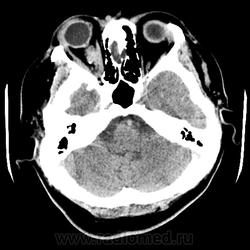

Женщина 48 лет, поступила с подозрением не ОНМК. На КТ -данных за ОНМК не обнаружено, но в правой орбите ретробульбарно мягкотканное образование +45HU, признаков деструкции и ремоделирования костных структур орбиты не наблюдается, медиальная и нижняя прямая мышца отчетливо не дифференцируются, зрительный нерв тесно прилежит к данному образованию. После КУ гомогенное накопление КВ и повышение плотности до +65HU. Экзофтальм. Жалобы на снижение зрения. Год назад делала МРТ ГМ, на снимке патологии орбит не увидел. Идиопатическая псевдоопухоль орбиты?

Поражение лор органов, ретробульбарного пространства.

Исключить гранулематоз с полиангиитом.

Гранулематоз Вегенера. интраорбитальная гранулема? Будем разбираться и Rg-графию ОГК посмотрим обязательно, если в легких гранулемы, то это он, спасибо за совет.